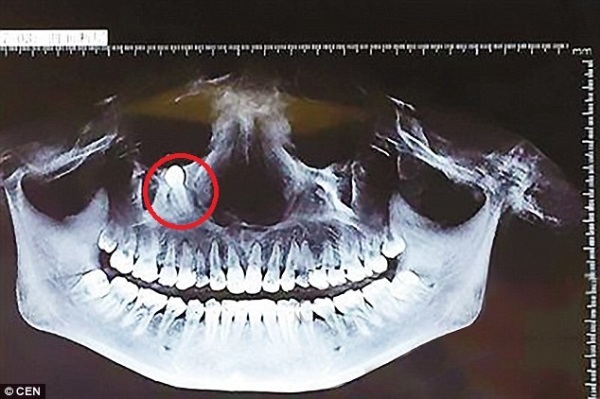

Khi tới bệnh viện, cô Tào mới ngã ngửa khi các bác sĩ cho biết đang có một chiếc răng mọc ngược lên trên và tiến về phía hốc mắt phải của cô. Họ cũng cảnh báo cô cần phẫu thuật sớm nếu không muốn mắt bị tổn thương vĩnh viễn.

Tại đây, các bác sĩ ở bệnh viện Đại Bình đã đồng ý tiến hành ca tiến phẫu thuật và lấy thành công lấy một chiếc răng dài gần 3cm khỏi khuôn mặt của chị Tào.

Theo các bác sĩ, nguyên nhân của tình trạng trên là do một chiếc răng sữa của chị Tào đã không rụng kịp thời nên chiếc răng bên dưới không thể mọc thế chỗ và di chuyển ngược lên.

Quá trình này đủ chậm rãi để bệnh nhân không cảm thấy đau đớn, nhưng một khi chiếc răng di chuyển lên tới hốc mắt thì bệnh nhân sẽ cảm thấy vô cùng khó chịu. Và nếu không được điều trị kịp thời, chiếc răng mọc ngược sẽ gây thương tổn không nhỏ cho mắt khiến thị lực bị ảnh hưởng nghiêm trọng.